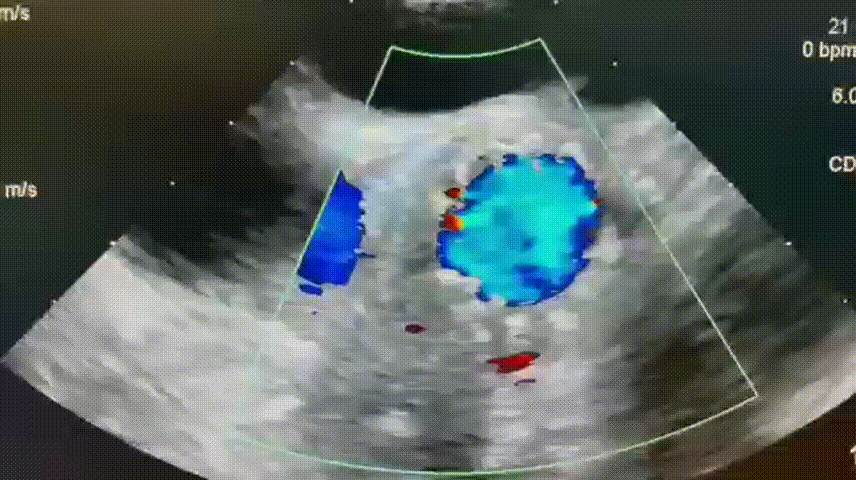

术后超声:

术后心超评估:瓣膜膨胀良好、无漏